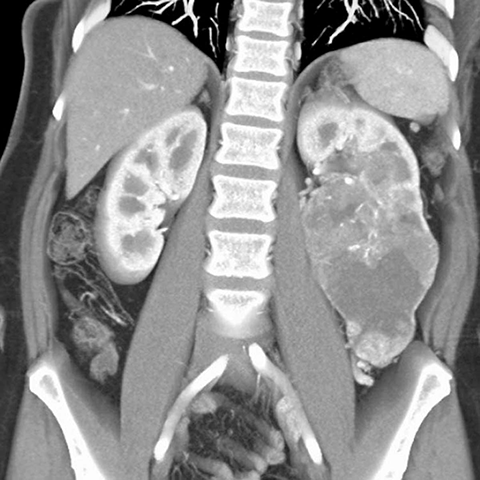

67-year-old male with flank mass and hematuria [1 of 4]